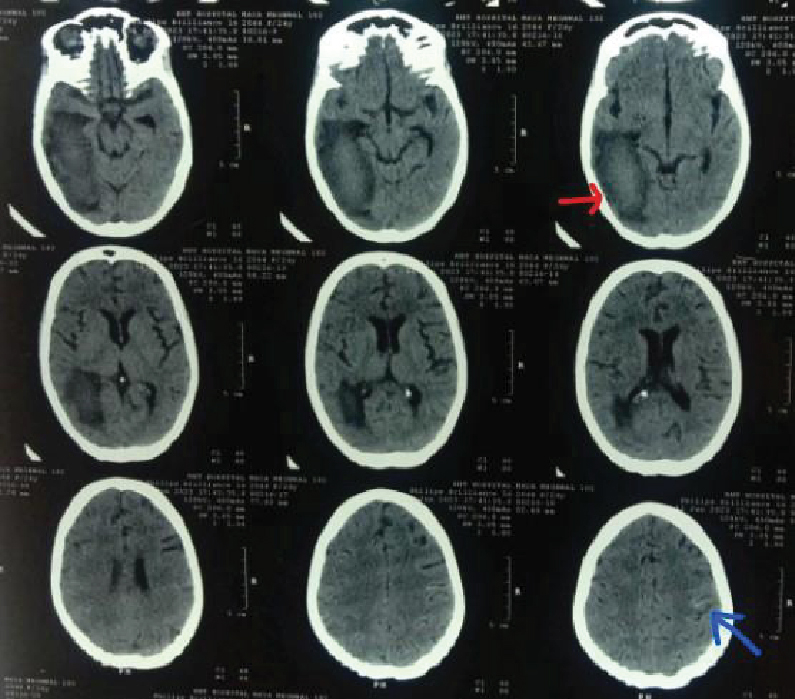

About 1.5 months back she had suffered an episode of generalized tonic-clonic seizures (GTCS) followed by loss of consciousness, she was admitted in some other hospital. An NCCT (non-contrast computed tomography) head (Fig. 2) was done which showed an acute intracranial hemorrhage in right parieto-occipito-temporal region. Considering it as vasculitis, the following investigations- antinuclear antibodies (ANA), double-stranded deoxyribonucleic acid (dsDNA), complete blood count (CBC), liver function test (LFT), renal function test (RFT), cerebrospinal fluid (CSF) adenosine deaminase (ADA) and a neuropanel of CSF for central nervous system (CNS) infections were also done. All the reports were normal except for moderate anemia. She was also diagnosed as primary hyperthyroidism for which she was put on antithyroid medications. She was started on steroids and DOTS ATT was continued, her condition improved and she was discharged after 20 days with tapering dose of steroids, antithyroid medications and iron supplements.

Figure 2. NCCT head showing intracranial hemorrhage in right parieto-temporal-occipital region (red arrows).

NCCT head revealed new subarachnoid hemorrhage (SAH) in left parietal lobe region with old intracerebral hemorrhage (ICH) changes (Fig. 3). Routine investigations were sent including CBC, LFT, RFT, thyroid profile. Chest X-ray showed multiple heterogeneous opacities in bilateral lung fields (Fig. 4). Bedside USG abdomen and pelvis showed heterogeneously enlarged uterus with echogenic mass seen in pelvis and bilateral adnexa are not visualized separately. There was also mild right-sided hydroureteronephrosis. Other investigations like serum vitamin B12, human immunodeficiency virus (HIV) enzyme-linked immunosorbent assay (ELISA); sputum for culture, acid fast bacilli (AFB), CBNAAT; ANA, cytoplasmic- antineutrophil cytoplasmic antibodies (cANCA), perinuclear-ANCA, antiphospholipid antibodies (APLA), coagulation profile, peripheral blood smear (PBS) were sent. The results are shown in Table 1.

Figure 3. NCCT head showing mild linear hyperdensity in left parietal region (blue arrow). Old ICH changes are also seen (red arrow).